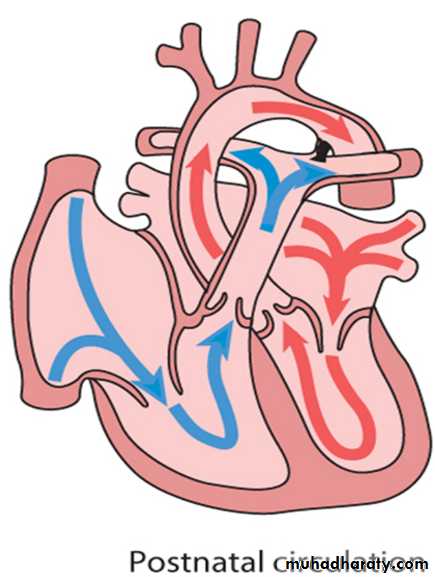

Circulatory changes at birth

In the fetus, the left atrial pressure is low, as relatively little blood returns from the lungs.

The pressure in the right atrium is higher than in the left, as it receives all the systemic venous return including blood from the placenta.

The ductus arteriosus shifts the blood from the pulmonary artery to the aorta.

The flap valve of the foramen ovale is held open, blood flows across the atrial septum into the left atrium and then into the left ventricle, which in turn pumps it to the upper body.

With the first breaths, resistance to pulmonary blood flow falls and the volume of blood flowing through the lungs increases sixfold. This results in a rise in the left atrial pressure. Meanwhile, the volume of blood returning to the right atrium falls as the placenta is excluded from the circulation. The change in the pressure difference causes the flap valve of the foramen ovale to be closed. The ductus arteriosus will normally close within the first few hours or days.